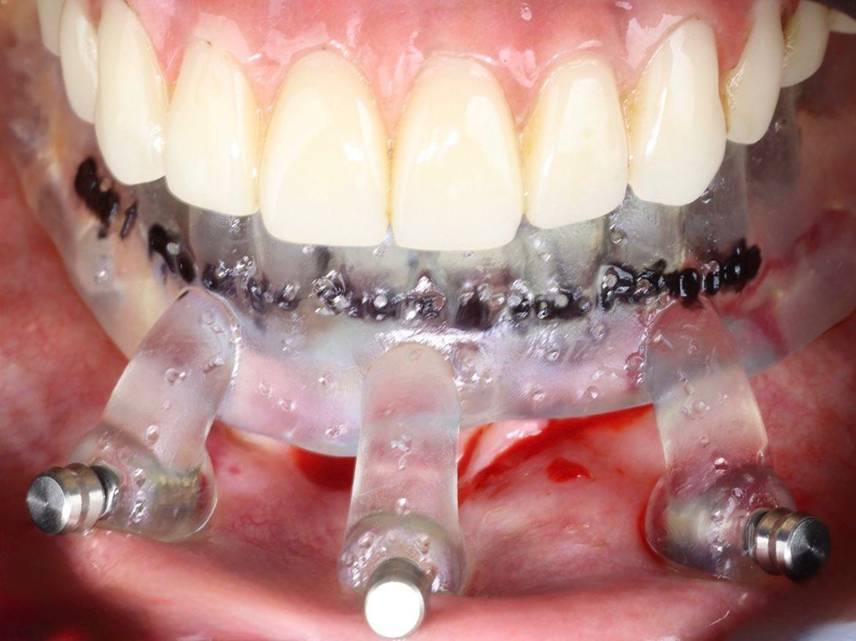

Paciente de 62 anos, do sexo feminino, sem comorbidades e história médica pregressa, apresentava severa reabsorção óssea em regiões anteriores e posteriores da mandíbula devido a uma peri-implantite (Figuras 1A e 1B). Feita a remoção dos implantes, a paciente optou por utilizar uma prótese total mucossuportada até a nova intervenção com prótese do tipo protocolo inferior. Após seis meses, a mandíbula encontrava-se cicatrizada (Figura 2). Como parte do protocolo diagnóstico, foi realizada tomografia computadorizada pela técnica do duplo DICOM. Com a severa perda óssea em região anterior de mandíbula, optamos por realizar a cirurgia de forma guiada, aumentando a previsibilidade e precisão da cirurgia. Os arquivos obtidos foram exportados para o software CoDiagnostiX, possibilitando a realização do planejamento reverso e o subsequente posicionamento virtual dos implantes (Figura 3). Com base no planejamento, optou-se pela instalação de quatro implantes Implacil Osstem CM AR Due Cone (3,5 x 7 mm), associados a mini-cônicos de 1,5 mm (Figuras 4A, 4B, 4C, 4D e 4E). A partir da tomografia da prótese da própria paciente, confeccionaram-se duas guias cirúrgicas: uma guia de pino de fixação (Figura 5) e uma guia de fresagem para a instalação dos implantes (Figura 6). Durante o procedimento cirúrgico, inicialmente foi posicionada a guia de pino de fixação para fresagem dos pinos de fixação e orientação da sequência cirúrgica (Figura 7). Após essa etapa, a guia foi substituída pela guia de fresagem dos implantes (Figura 8), utilizada para a fresagem e inserção dos implantes planejados (Figura 9). Concluída a instalação, optou-se por seguir o fluxo analógico, com a adaptação dos mini-cônicos 1.5 mm (Figura 10), realização da transferência de moldagem com silicona de adição leve e sutura com fio absorvível Vycril 6-0. O guia inicial foi adaptado com broca Maxicut, possibilitando sua utilização como molde de orientação para o laboratório protético (Figura 11). Após a moldagem, foram posicionadas as tampas de proteção sobre os implantes. Na fase protética, transcorridas 48 horas do procedimento cirúrgico, foi realizada a prova clínica da barra metálica e dos dentes (Figura 12). Na etapa subsequente, 72 horas após a cirurgia, procedeu-se à instalação e entrega do protocolo mandibular inferior e radiografia prévia, reabilitando funcional e esteticamente a paciente em curto espaço de tempo (Figuras 13A e 13B).